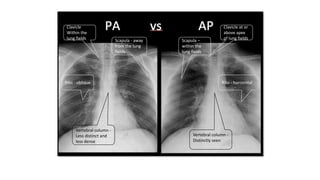

AP view or PA view

AP view PA view

Clavicle At or above apex

of lung fields

Within the lung

fields

ribs horizontal oblique

scapula Within lung

Away from the

lung fields

Vertebral

column

Distinctly seen Less distinct and

less dense

Clavicle in / scapula out -> is PA view